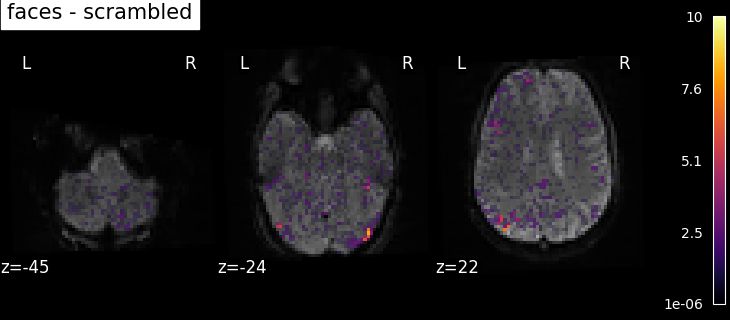

8.2.3.1. Computing contrasts¶

To get more interesting results out of the GLM model, contrasts can be computed between regressors of interest.

The nilearn.glm.first_level.FirstLevelModel.compute_contrast function can be used for that. First,

the contrasts of interest must be defined. In the spm_multimodal_fmri dataset referenced above, subjects are

presented with ‘normal’ and ‘scrambled’ faces. The basic contrasts that can be constructed are the main effects

of ‘normal faces’ and ‘scrambled faces’. Once the basic_contrasts have been set up, we can construct more

interesting contrasts like ‘normal faces - scrambled faces’.

And finally we can compute the contrasts using the compute_contrast function. Refer to Single-subject data (two runs) in native space for the full example.

The activation maps from these 3 contrasts is presented below: